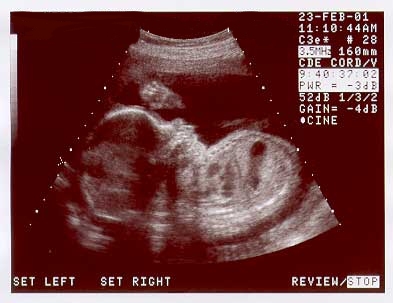

BABY YAWNING!!! 25Wks.

Week 25:   Baby Nicolas yawning!  Motion captured during U/S session on  Feb. 23, 2001.

These are Nicolas' u/s pics taken on Feb. 23. 2001, at 25 wks.

Image sequence 1 of 6